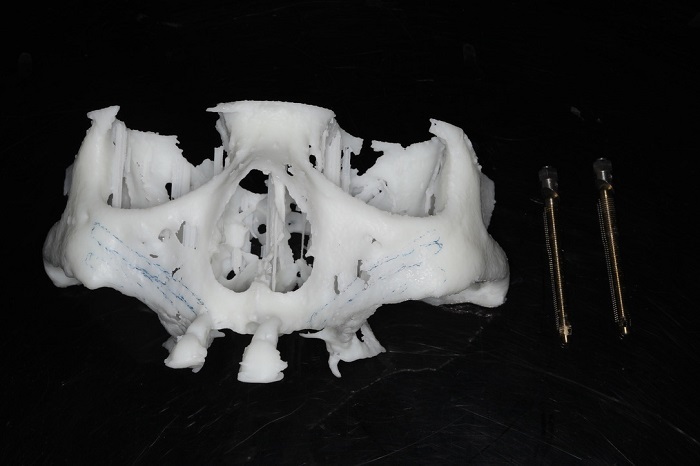

据悉,患者潘女士54岁,由于重度牙周炎导致全口牙齿缺失,严重影响面容及咀嚼功能,因颌骨严重萎缩无法进行活动义齿修复,遂来色情网站 种植科要求行上颌稳固的修复。通过检查发现潘女士上下颌骨骨量严重不足,经反复比对和考量,刘鑫主任制定了对患者上颌骨进行穿颧种植修复、下颌骨通过神经游离进行种植的方案。经过患者与家属深思熟虑后,接受了行穿颧种植术的建议。治疗组通过专业三维设计软件规划植体,口腔颌面外科和种植科专家共同完成了穿颧种植手术。患者术后第一天情况良好,无明显肿胀,精神状态佳。